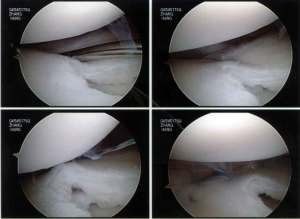

Firstly the discoid portion of the lateral meniscus was removed arthroscopically as shown:

Next, the torn part of the meniscus was repaired to the capsule using a combination of all-inside and inside-out meniscus repair technique.